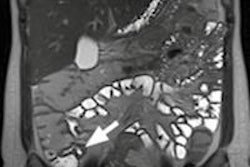

| Images show patient with terminal ileitis. CT (above) and gadolinium-enhanced MR enterography (below) show abnormal wall thickening. Both readers agreed on the interpretation of images. All images courtesy of David Grand, MD. |

![]() |